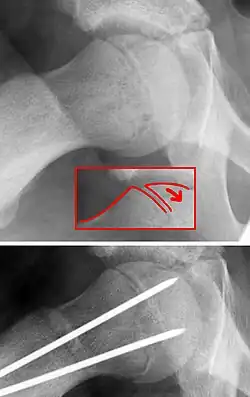

Auf einem Röntgenbild der Hüften, insbesondere einer Beckenübersichtsaufnahme, ist die Ablösung des Gelenkkopfes nicht immer gut zu sehen. Wichtig ist daher eine zusätzliche axiale Aufnahme in Lauenstein-Projektion beidseits, auf welcher die Fehlstellung der Epiphyse gut erkannt werden kann. An dieser Aufnahme wird der Abrutschwinkel bestimmt. Aus diesem Winkel ergeben sich therapeutische Konsequenzen.

Um eine mögliche Femurkopfnekrose zu vermeiden und eine spätere Belastbarkeit des betroffenen Gelenkes zu erreichen, ist die operative Fixierung notwendig. Dazu dienen bei jungen Patienten mit noch deutlichem Restwachstum Bohrdrähte, die parallel zum Schenkelhals über die Wachstumsfuge in die Epiphyse vorgeschoben werden. Bei erheblichem akuten Abrutsch muss erst der Hüftkopf durch Innenrotation und Zug reponiert werden. Bei älteren Kindern ohne wesentliches Restwachstum (Y-Fuge bereits verschlossen) werden Schrauben mit kurzem Gewinde in gleicher Richtung in den Hüftkopf eingebracht. Der Eingriff wird Epiphyseodese genannt, die Wachstumsfuge wird überbrückend stabilisiert. Nach Abschluss des Wachstums wird das Osteosynthesematerial (Drähte oder Schrauben) entfernt.